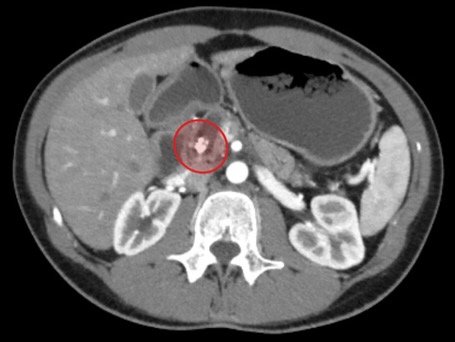

Під час нещодавнього планового обстеження медики виявили несподівану патологію — каміння у підшлунковій залозі, що є вкрай рідкісним і небезпечним станом. Таке захворювання може призвести до гострого панкреатиту або механічної жовтяниці через порушення відтоку жовчі та панкреатичних соків.

Ірині виконали мініінвазивну лапароскопічну операцію Фрея, під час якої видалили конкременти, очистили протоки та частково висікли уражені тканини підшлункової залози. Втручання пройшло успішно та забезпечило швидке відновлення.